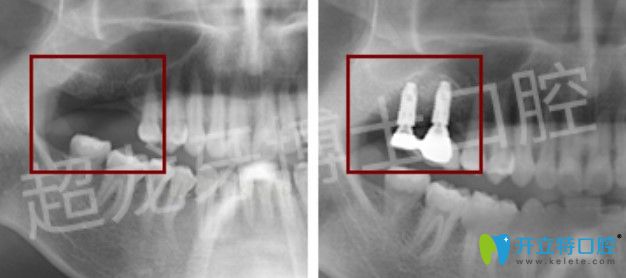

牙博士口腔成人齙牙矯正+多顆牙種植案例:

矯正案例:

牙齒情況:齙牙

矯正方式:金屬自鎖托槽矯正

種植案例:

牙齒情況:多顆牙缺失

種植技術(shù):微創(chuàng)無痛種植技術(shù)